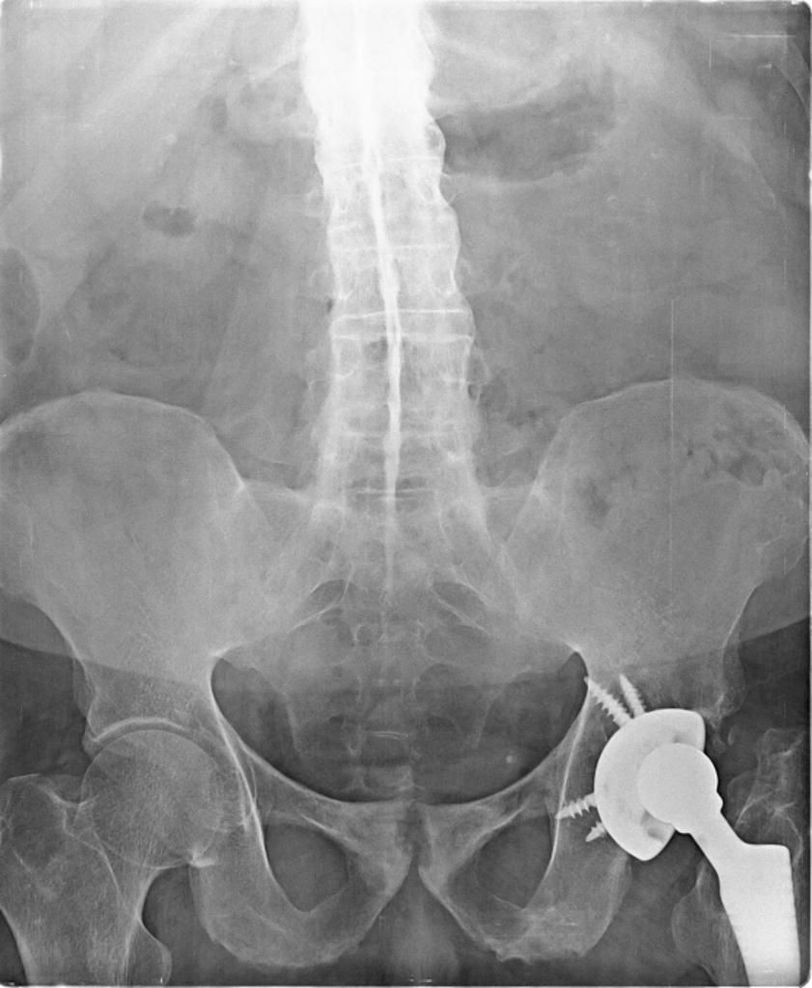

🔸Bamboo spine is a radiographic feature seen in ankylosing spondylitis that occurs as a result of vertebral body fusion by marginal syndesmophytes. It is often accompanied by fusion of the posterior vertebral elements as well. 🔸 A bamboo spine typically involves the thoracolumbar and/or lumbosacral junctions and predisposes to unstable vertebral fractures and Andersson lesions. 🔸In a bamboo spine, the outer fibers of the annulus fibrosus of the intervertebral discs ossify, which results in the formation of marginal syndesmophytes between adjoining vertebral bodies. The resulting radiographic appearance, therefore, is that of thin, curved, radiopaque spicules that completely bridge adjoining vertebral bodies. 🔸There is also accompanying squaring of the anterior vertebral body margins with associated reactive sclerosis of the vertebral body margins (shiny corner sign). Together these give the impression of undulating continuous lateral spinal borders on AP spinal radiographs and resemble a bamboo stem; hence the term bamboo spine. 🔸Source: radiopedia